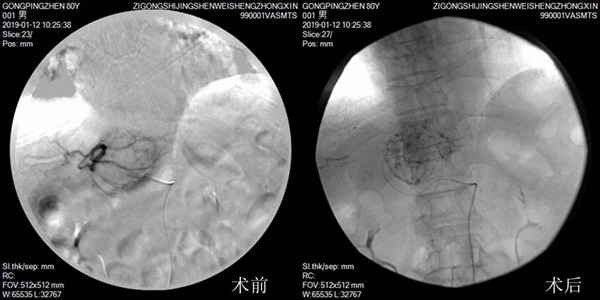

近日,我院老年肿瘤科成功为一名80岁高龄的肝血管瘤患者开展了介入手术治疗,标志着老年肿瘤科开启了介入治疗的新篇章。

现年80岁高龄的龚大爷于两年前查出肝脏上长了一个良性的血管瘤,大小约2厘米。近期龚大爷到市老年病医院复查时,显示该肝血管瘤已经长到了7厘米左右,如果不进行及时治疗,血管瘤尺寸较大且长势较快,随时有可能破裂出血危及生命。但常规手术切除麻醉、手术风险大,龚大爷年事已高,身体承受不了,同样存在较大的风险。

根据龚大爷的病情,市老年病医院老年肿瘤科请到了四川省肿瘤医院李政文教授到院会诊,决定为龚大爷实施无创介入手术治疗。在李政文教授的指导下,手术进行得很成功,仅用了不到1个小时便完成了手术,术后龚大爷恢复得很好,两三天后便出院。

据市老年病医院老年肿瘤科副主任丁平军介绍,介入治疗是在医学影像设备的引导下,将药物注射于瘤体血管内,对体内病灶进行局部治疗,治疗切口(穿刺点)仅有针尖大小。相比常规手术,介入治疗具有无痛苦、恢复快、创伤小等优点,可算是名副其实的“微创”手术治疗,术后住院时间短,也减少了患者的医疗费用。